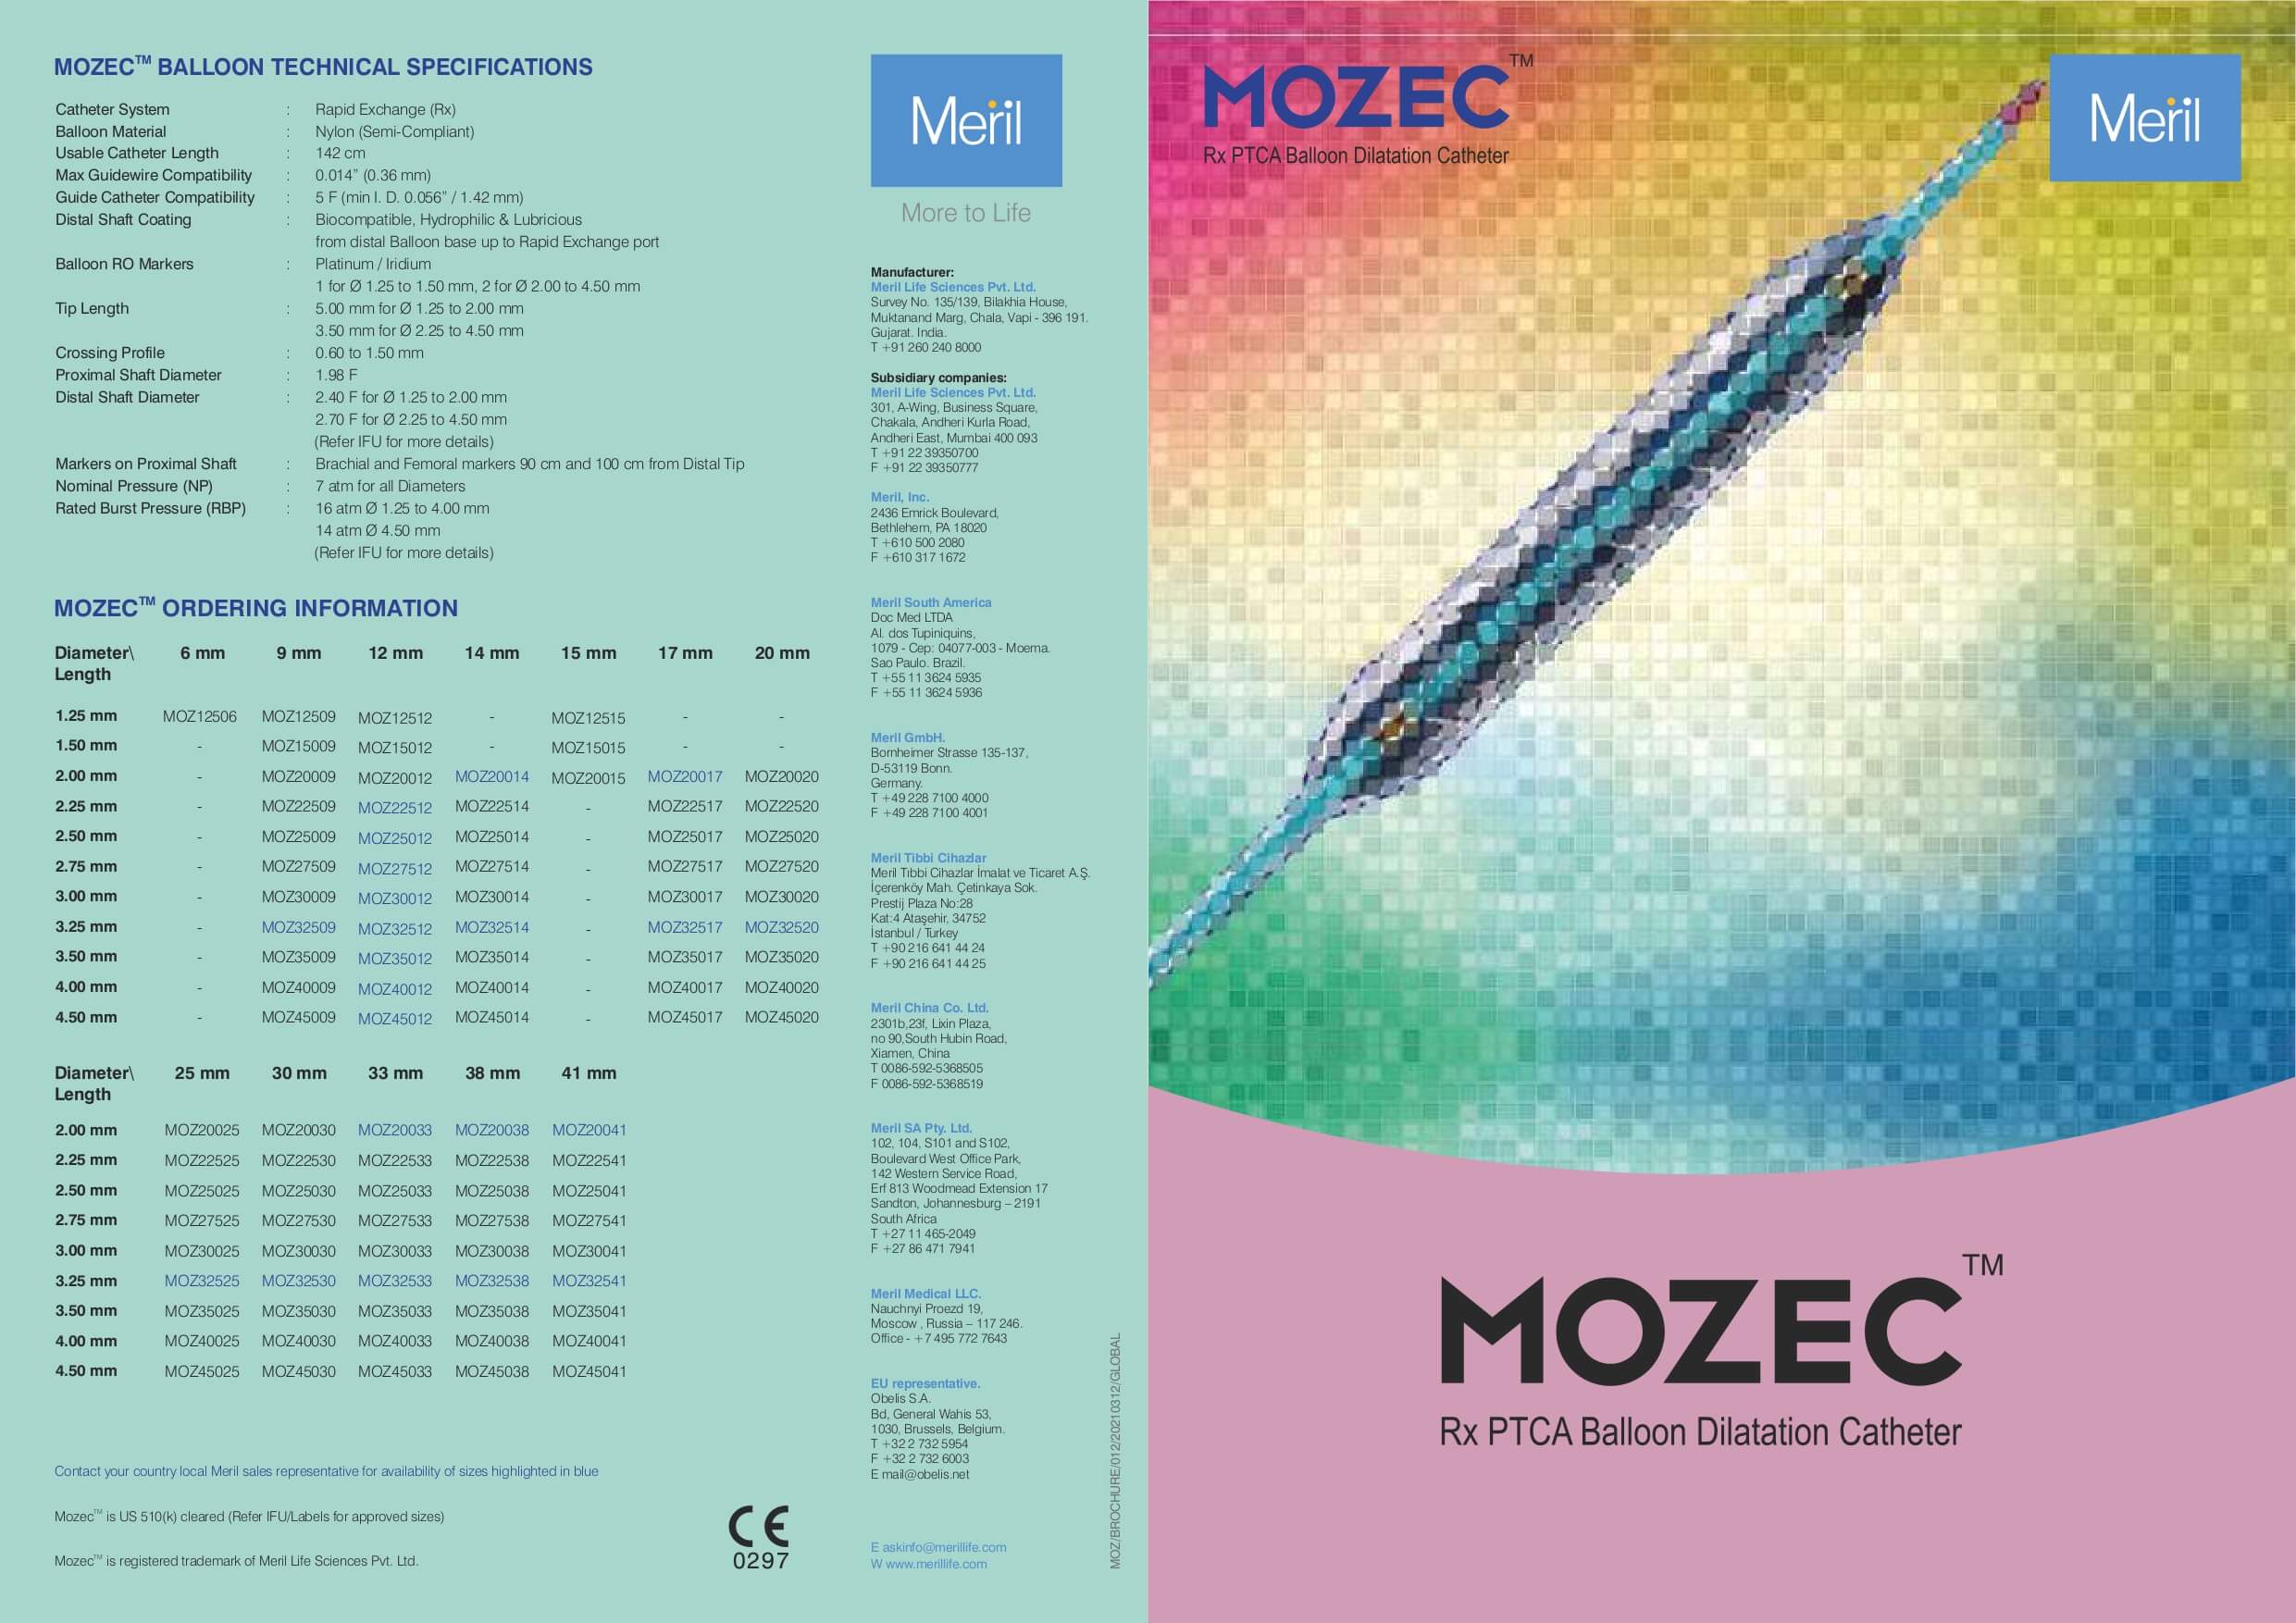

بالون دارویی کرونری MOZEC SEB برای انجام آنژیوگرافی، کاربرد دارد. این بالون از یک سیستم داروسازی جدید با فناوری نانو برای رها سازی کنترل شده دارو استفاده میکند و ویژگیهای خاص آن از نظر ابعاد، جنس و فشار قابل تحمل، این بالون را به گزینهای مناسب جهت انجام مداخلات عروقی تبدیل کرده است.